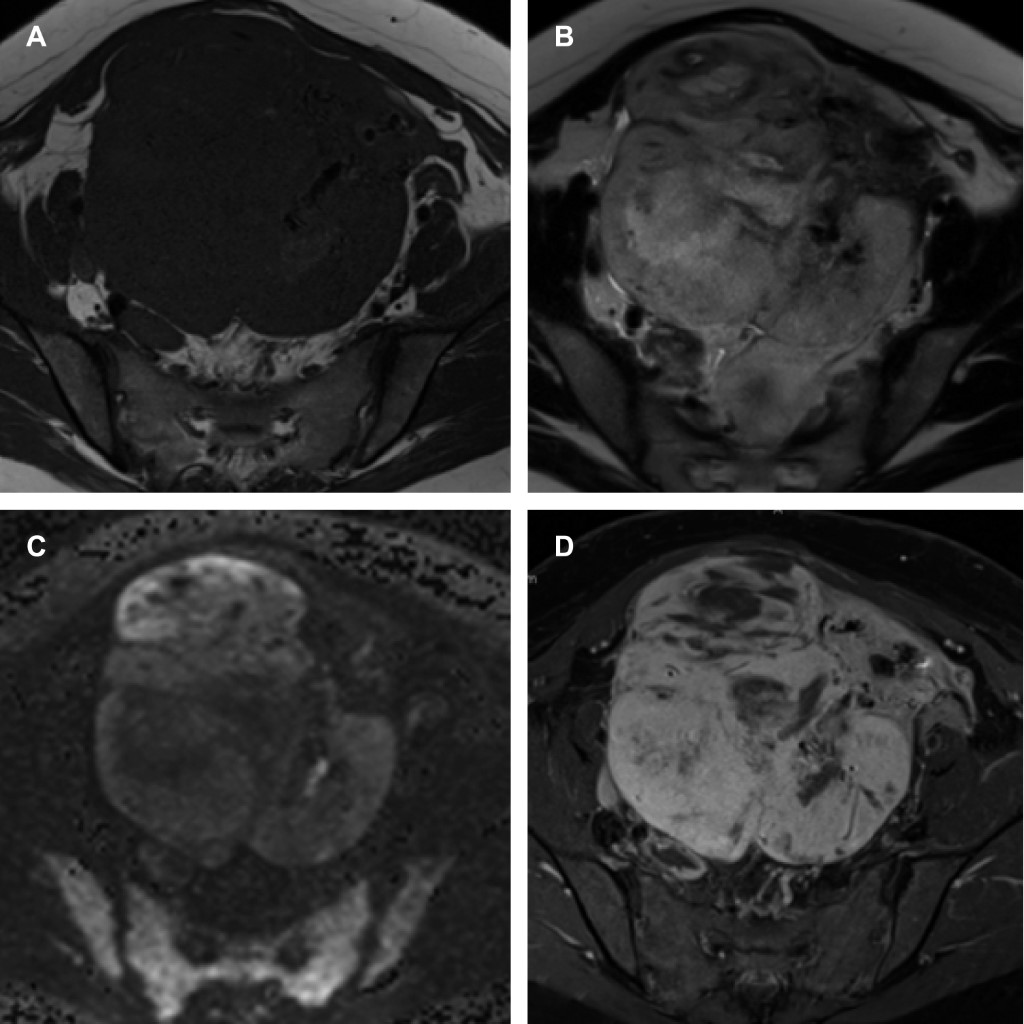

Se realiza resonancia magnética de pelvis con secuencias T1, T2, difusión y T1 contrastada que demuestran neoplasia uterina, que abarca desde el cuello hasta el fondo, de bordes lobulados y márgenes mal definidos, con eje mayor de 13.3 cm y un volumen aproximado de 919 cm3, con intensidad de señal baja en T1 e intensidad de señal heterogénea intermedia-alta en T2 con extensas zonas de necrosis central, áreas sólidas hipervasculares y zonas de hemorragia que sugieren el diagnóstico de leiomiosarcoma uterino (Figura 2).

Figura 1

Figura 2